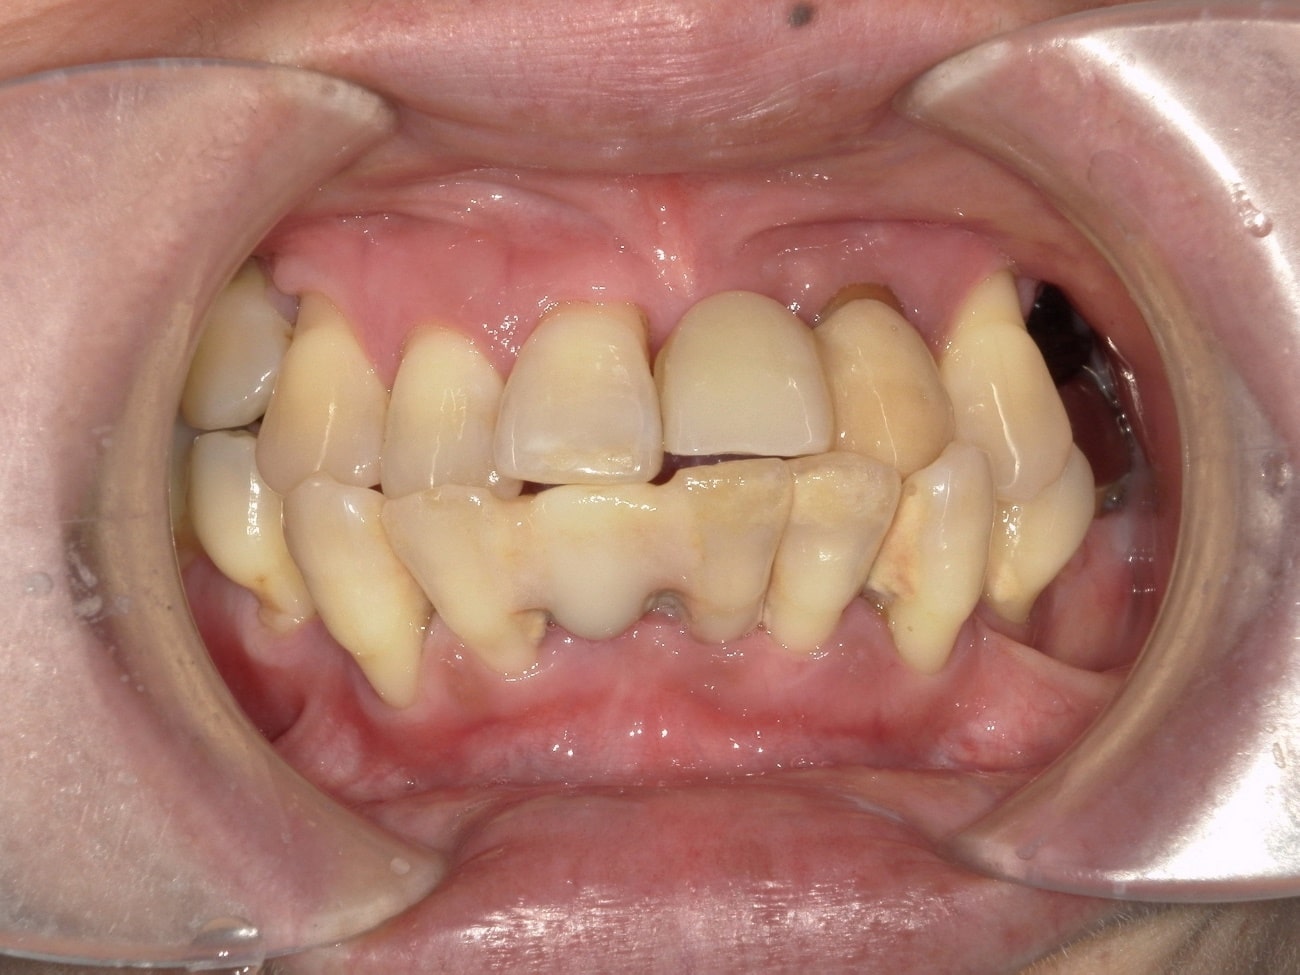

治療前の画像。重度の歯周病の患者様です。